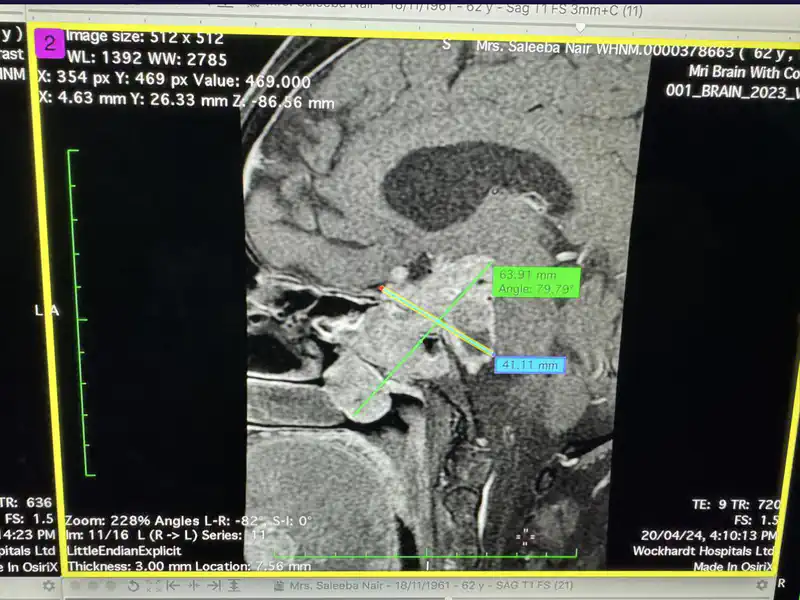

Dr Chandraveer Singh said “This patient presented with persistent nasal obstruction, episodes of giddiness, loss of appetite, and occasional headaches without any past medical history. Initial examination revealed the presence of a big mass in the Nasopharynx. Her nasal endoscopy, CT scans and Paranasal Sinus computed Tomography (PNS) tests revealed a large pituitary tumor measuring 7.3 x 4 x4.9 cm, extending from the Brain to the frontal bone and encroaching upon the Nasopharynx. The patient was diagnosed with Pituitary Adenoma (a benign or noncancerous growth on the pituitary gland) with an unknown cause. Macroadenomas, larger adenomas measuring about 1 centimeter or more were spotted in this case. This tumor is rare and is seen in 5 per 1 lakh population. Witnessing such a large tumor was unusual, indicating the need for a delicate surgery as the tumor was also interfering with the patient’s ability to do the daily chores with ease.